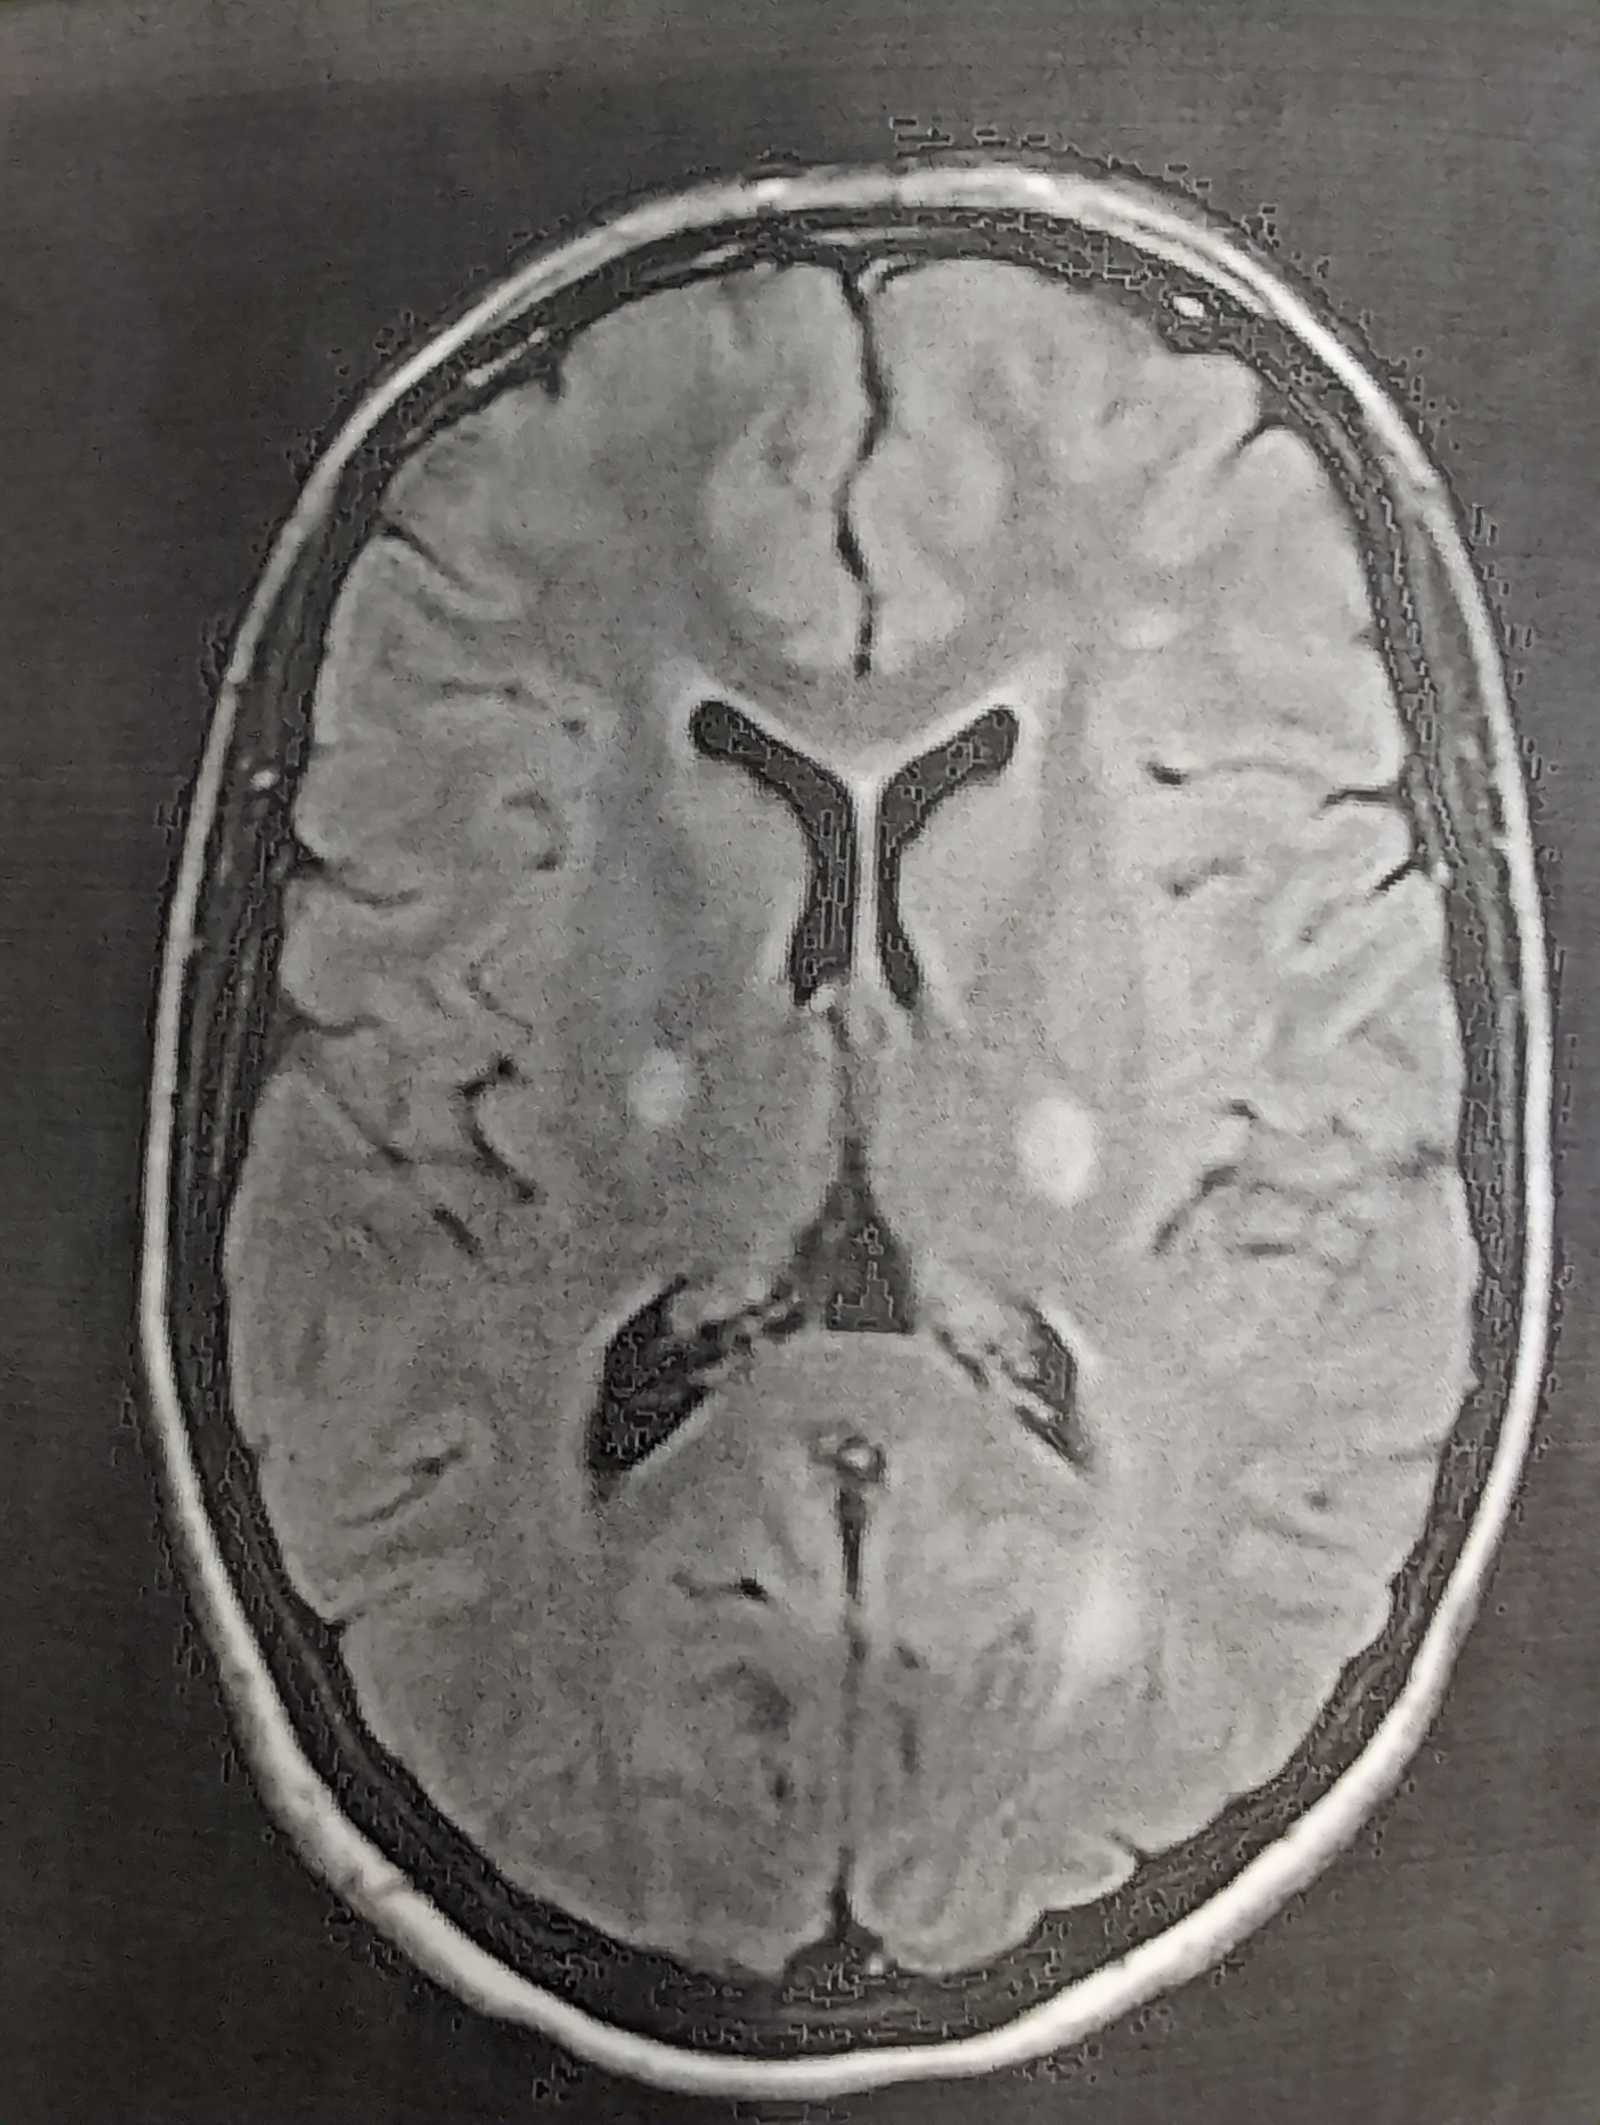

When I reached the ER I was immediately given a contrast MRI of my brain, and the results came quickly. The MRI shows signs of demyelination, which is when the myelin sheaths that protect the nerve fibers deteriorate. This inhibits the communication between my nerve cells and my body. I was admitted to MedSurge from the ER, and they have been pushing high dose steroids through an IV for 5 days. They are certain I have multiple sclerosis, but I will need to wait until my lumbar puncture results come back to determine the type. (More info after picture)